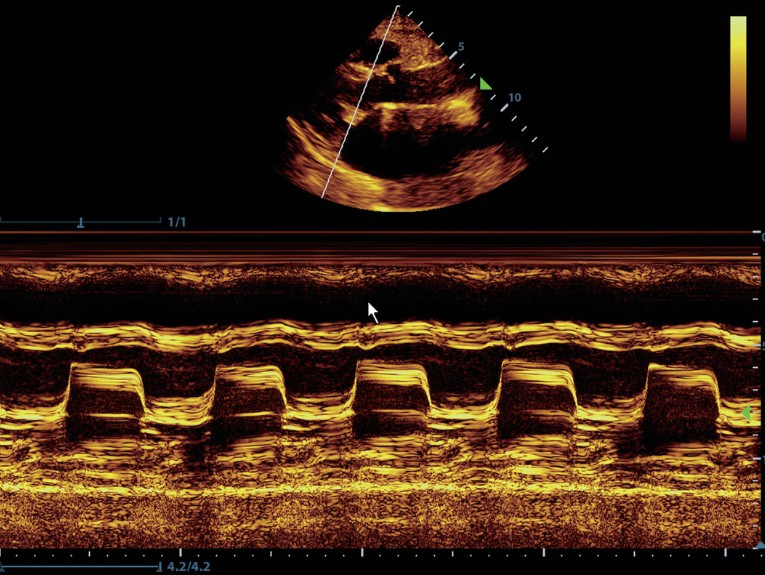

Клинические изображения